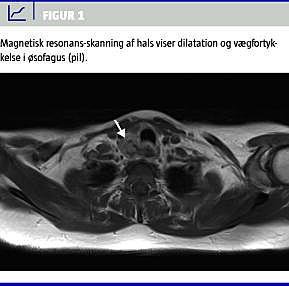

Billeddiagnostik (magnetisk resonans-skanning og computertomografi) viste en ca. 1,5 × 4 cm stor uregelmæssig dilatation af øsofagus og vægfortykkelse 4 cm efter afgangen. I jugulum sås en 16 mm stor cystisk forandring ved den palpable knude fortil på halsen og forstørrede lymfeknuder i mediastinum (Figur 1 ).